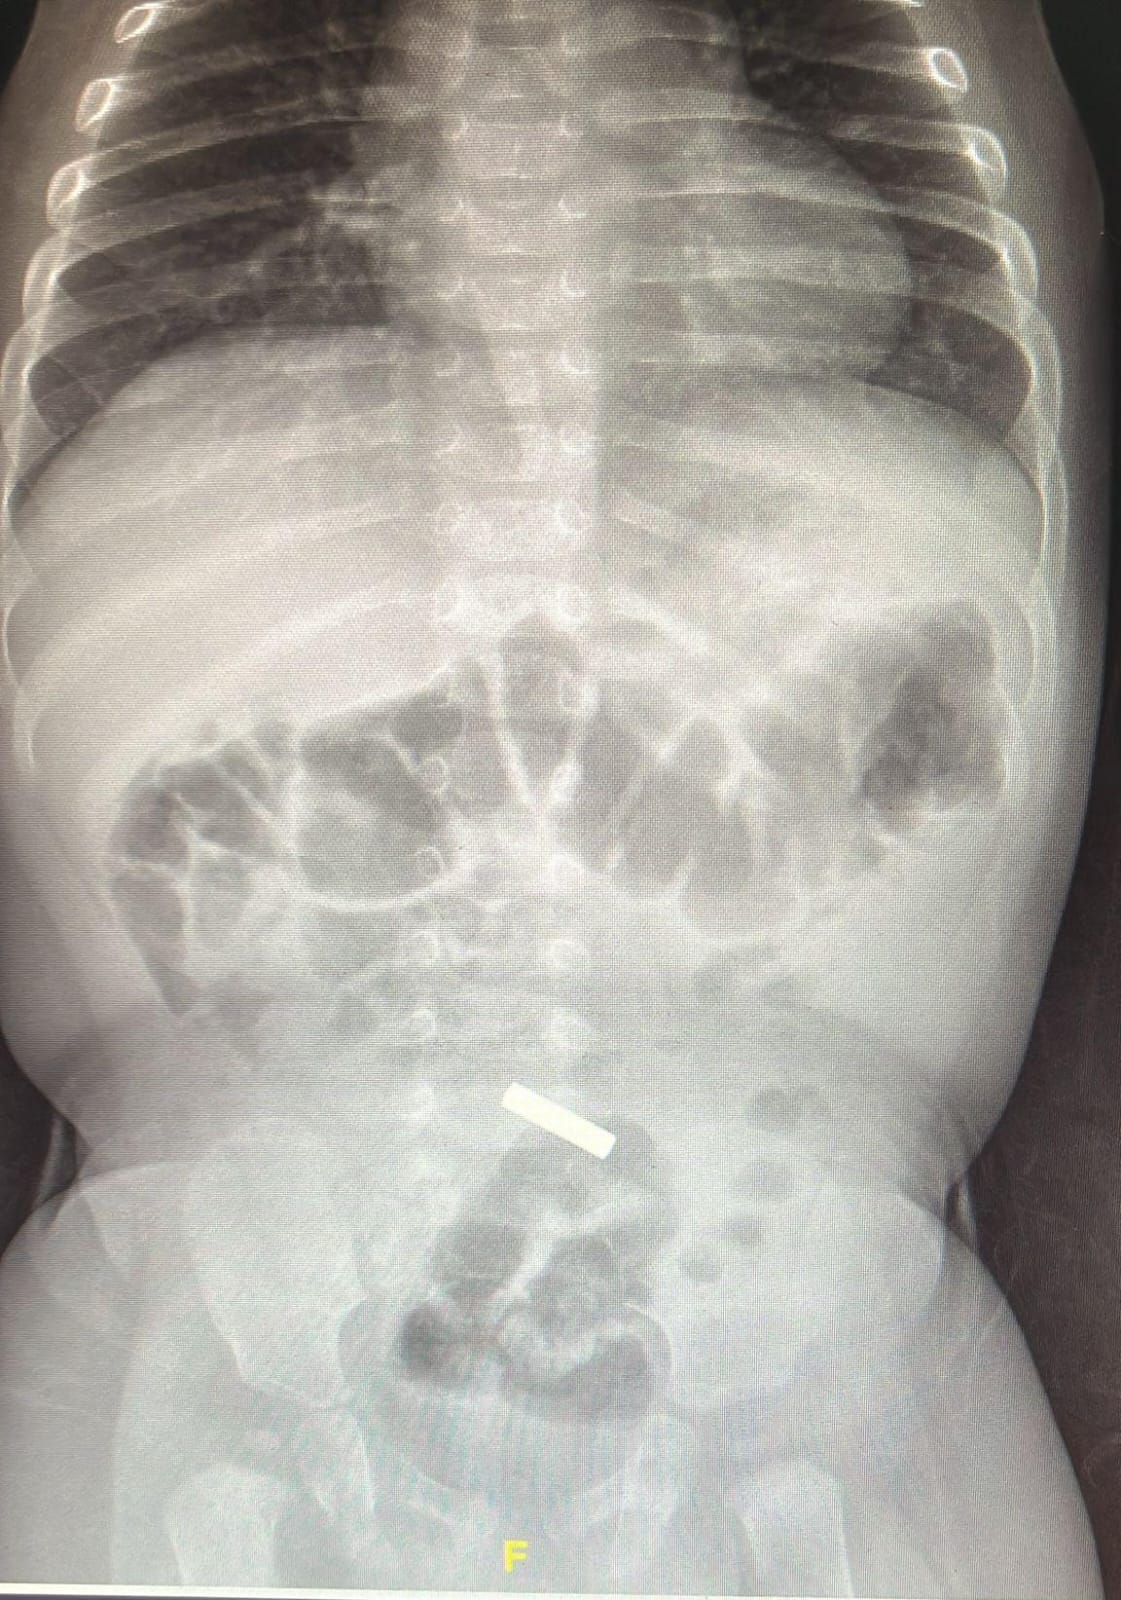

وصل الى المركز الطبي "تسفون" بوريا طفل يبلغ من العمر 11 شهرا بعد ان لاحظ اهل الطفل انه يعاني من درجة حرارة عالية وتقيؤ. وقد خضع الطفل للفحوصات اللازمة

صورة من المركز الطبي ‘تسفون‘

في قسم الأطفال في المركز الطبي، واتضح بعد اجراء تصوير اشعة للطفل انه على ما يبدو ابتلع قطعة معدنية استقرت في الأمعاء الدقيقة.

وتحدث الدكتور سعيد أبو زيد مدير قسم الأطفال في المركز الطبي "تسفون" مشيرا الى " ان الطفل على ما يبدو عانى من الحمى الشديدة والتقيؤ بسبب مرض فيروسي، لكن يتم أيضاً فحص احتمال أن يكون الجسم الغريب الذي ابتلعه هو الذي تسبب في ضرر موضعي أدى إلى ذلك" .

وأضاف د. أبو زيد مشيرا الى "ان ابتلاع الأغراض الصغيرة تعتبر خطيرة جدا على حياة الأطفال بما في ذلك ابتلاع القطع المعدنية وخاصة البطاريات الصغيرة والتي تؤدي الى مخاطر عديدة. فإذا علقت هذه القطع الغريبة في المريء فإنها من الممكن ان تتسبب بجراح وبالتالي تؤدي الى التهاب شديد وخطير، وفي هذه الحالة لا بد من إزالة الجسم الغريب فوراً. ومع ذلك، في هذه الحالة، كانت القطعة المعدنية قد مرت بالفعل عبر المريء وتم العثور عليها في منطقة الأمعاء. لهذا نحن الآن كطاقم طبي أكثر اطمئنانا ونتوقع أنها ستخرج في اليوم التالي دون الحاجة لأي تدخل طبي" .